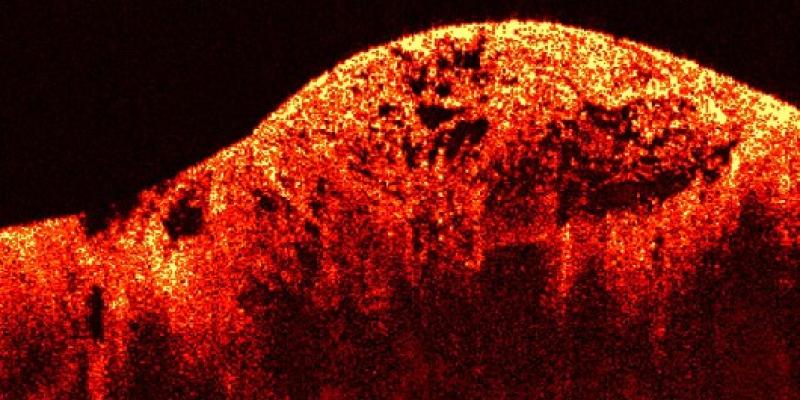

En definitiva, son un tipo de cáncer que se origina en los tejidos blandos (músculos, grasa, vasos sanguíneos, nervios, tendones, ligamentos y otros tejidos conectivos) o en los huesos. A diferencia de los carcinomas (que se originan en células que recubren órganos o glándulas, como la piel o el revestimiento intestinal), los sarcomas son de origen mesenquimal.